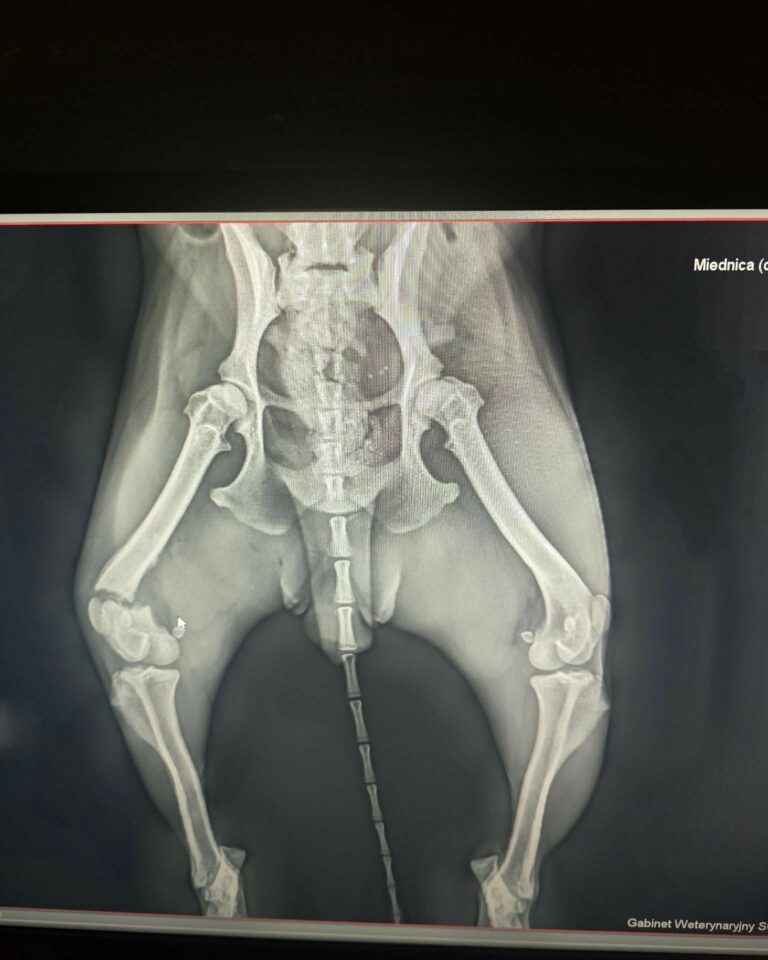

RTG ujawniło dramatyczną prawdę: poważne złamanie przynasadowe prawej kości udowej. To oznacza kolejną operację, zaplanowaną prawdopodobnie na środę.